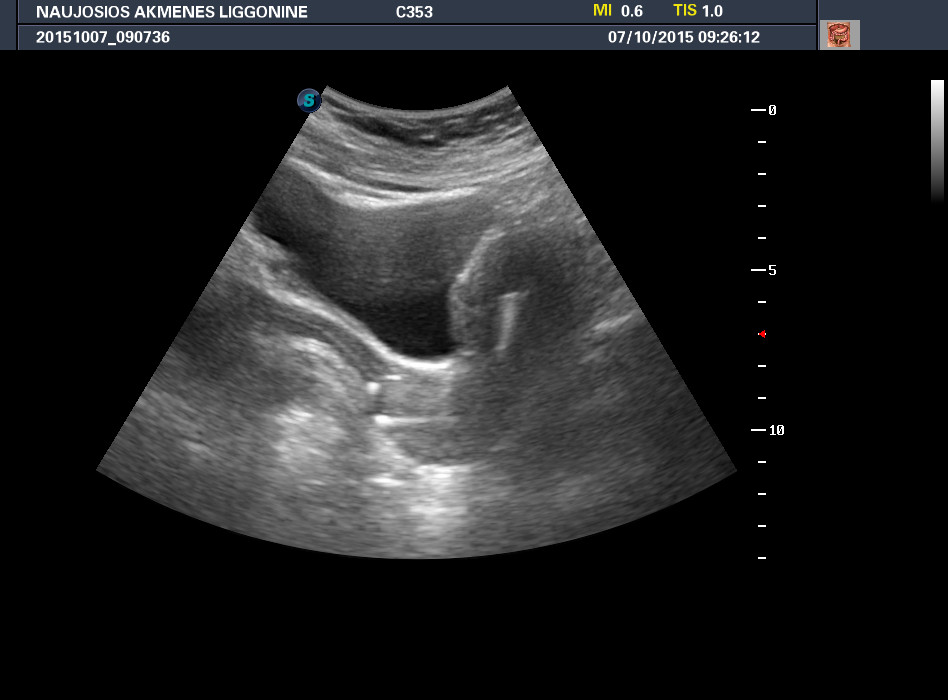

УЗИ - ВМС

Смущает форма и положение ВМС в матке - чувство что оно продолжается в шейку и даже перфорирует её.

Что за девайс такой? - ни разу подобного не видел.